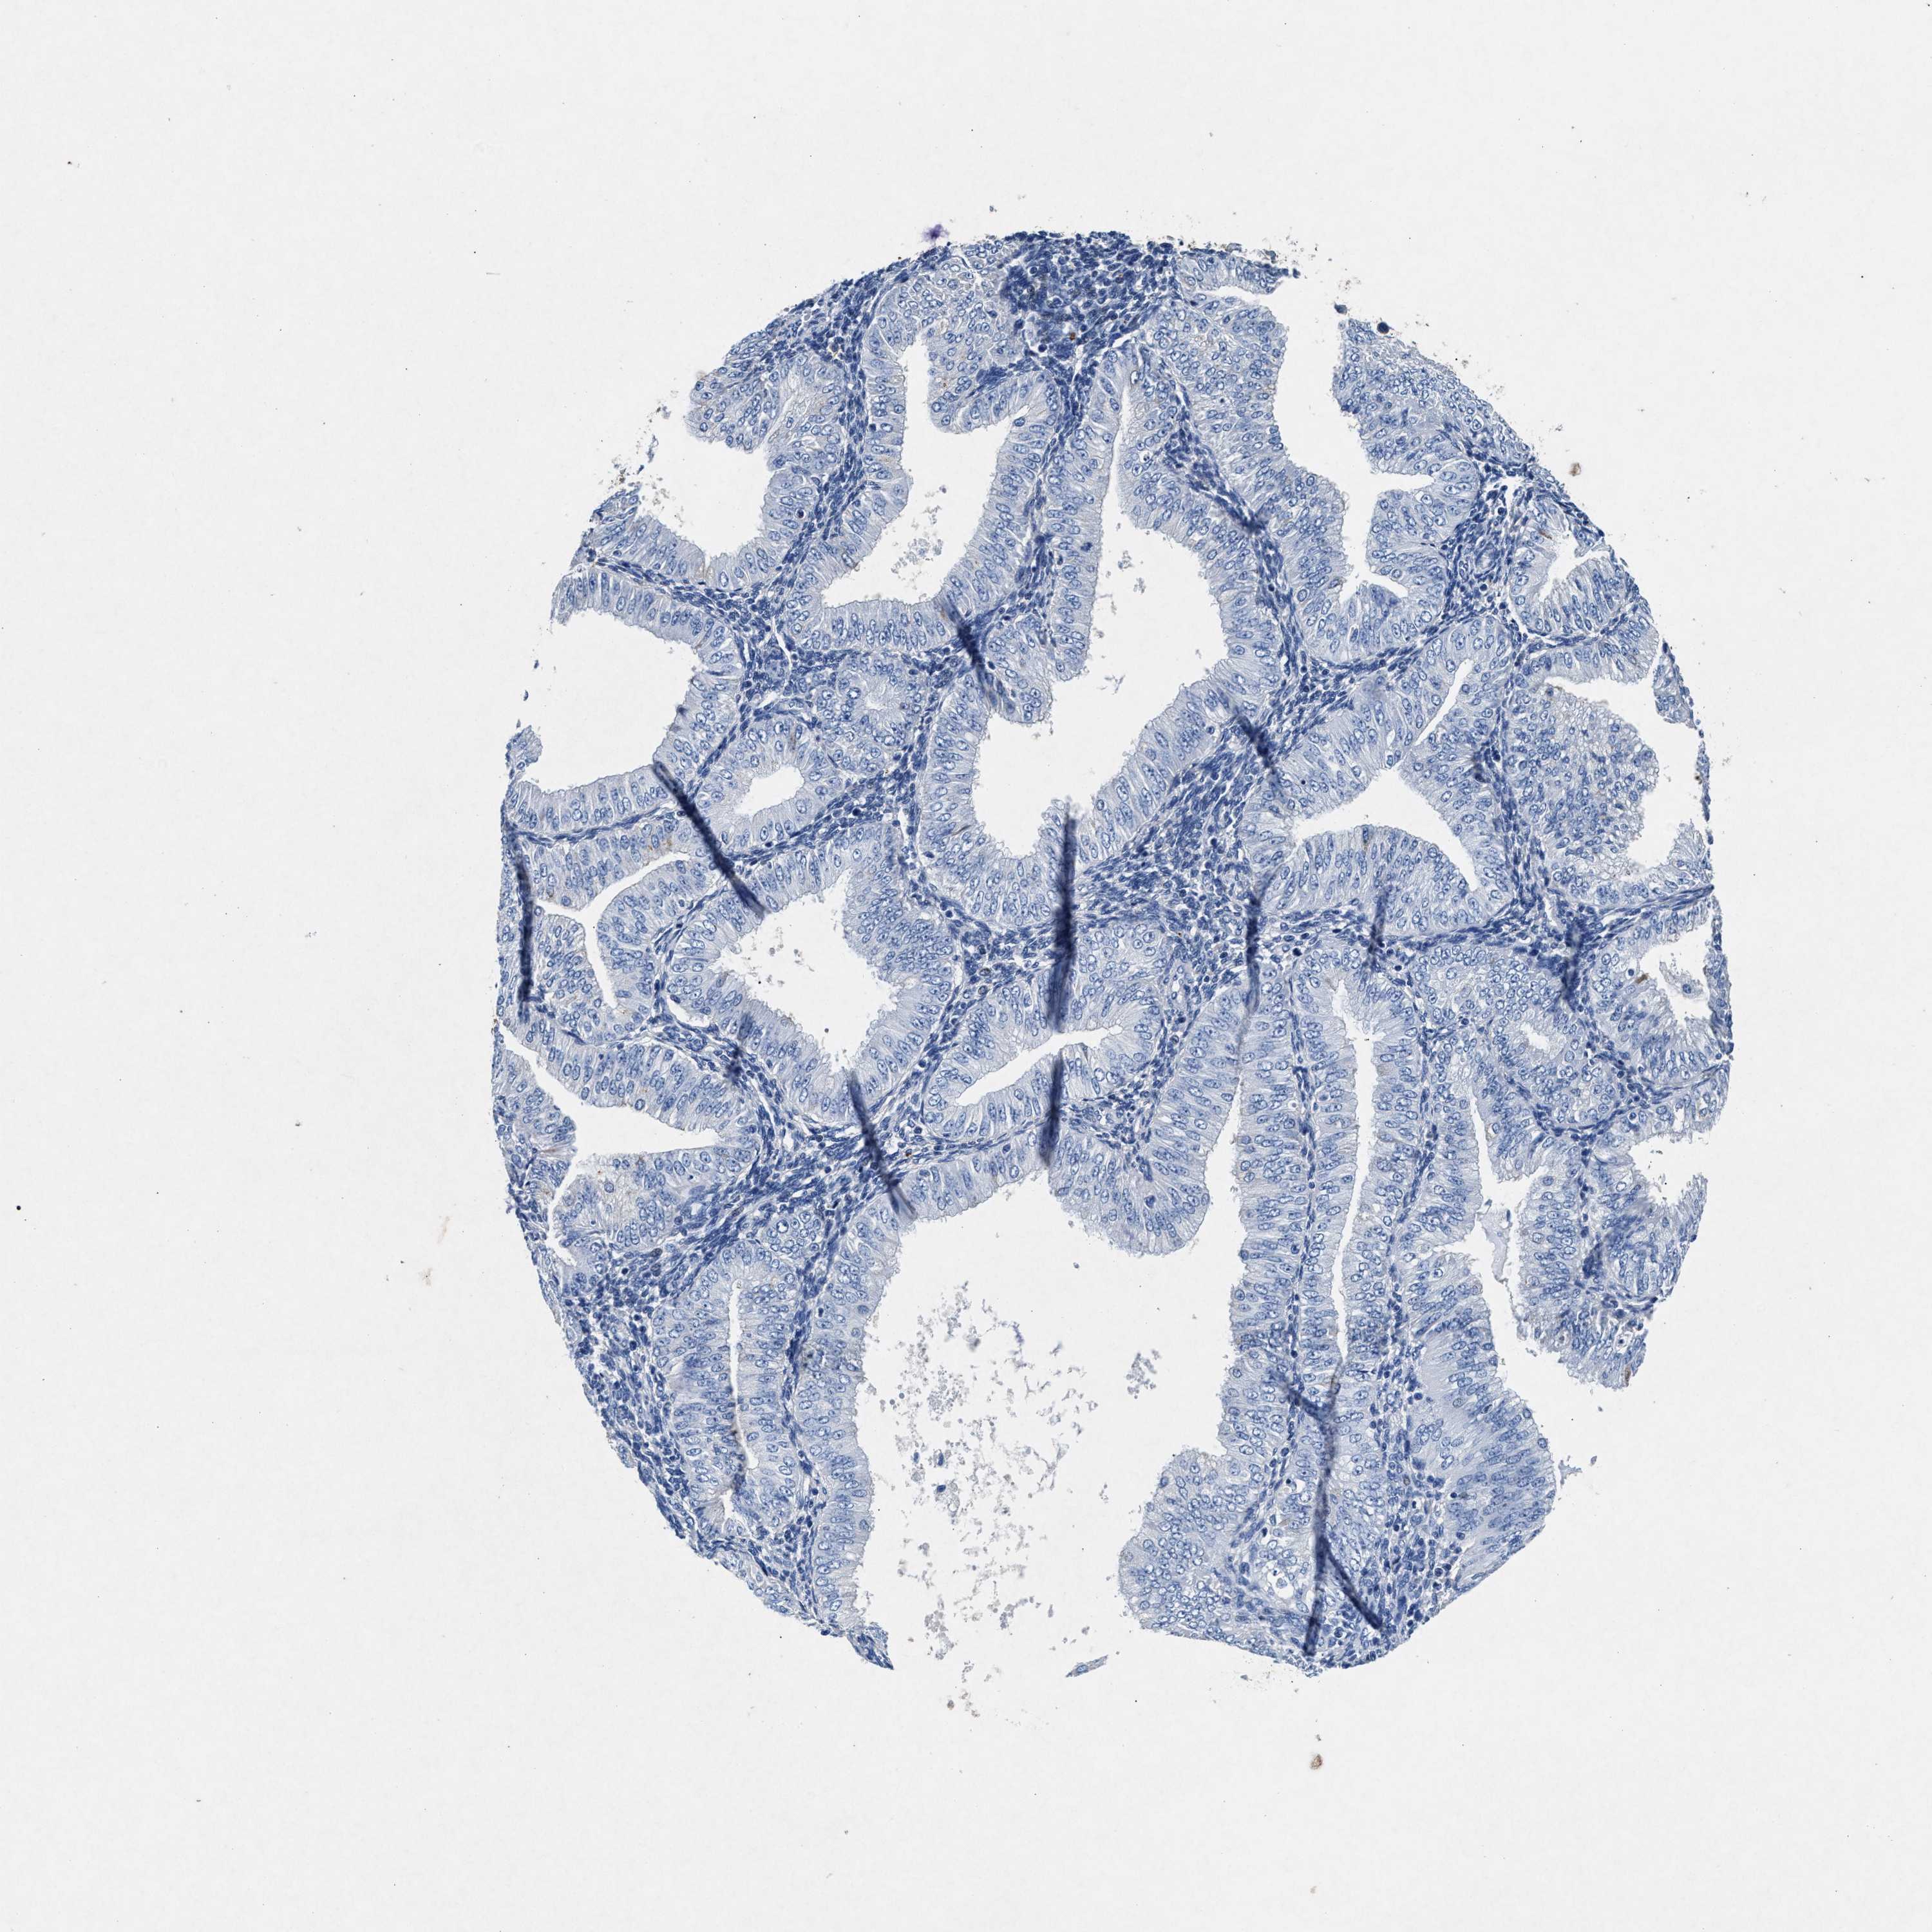

ENDOMETRIAL CANCER - Protein expressioni

A mouse-over function shows sample information and annotation data. Click on an image to view it in a full screen mode. Samples can be filtered based on level of antibody staining by selecting one or several of the following categories: high, medium, low and not detected. The assay and annotation is described here.

Note that samples used for immunohistochemistry by the Human Protein Atlas do not correspond to samples in the TCGA dataset.

Antibody stainingi

Antibody staining in the annotated cell types in the current human tissue is reported as not detected, low, medium, or high, based on conventional immunohistochemistry profiling in selected tissues. This score is based on the combination of the staining intensity and fraction of stained cells.

Each image is clickable and will lead to virtual microscopy that enables deeper exploration of all samples and also displays staining intensity scores, fraction scores and subcellular localization as well as patient and tissue information for each sample.

Antibody HPA039061

Antibody HPA039062

Antibody CAB015442

Antibody CAB022600

Staining

High

Medium

Low

Not detected

Intensity

Strong

Moderate

Weak

Negative

Quantity

>75%

75%-25%

<25%

None

Location

Nuclear

Cytoplasmic/membranous

Cytoplasmic/membranous,nuclear

Adenocarcinoma, NOS